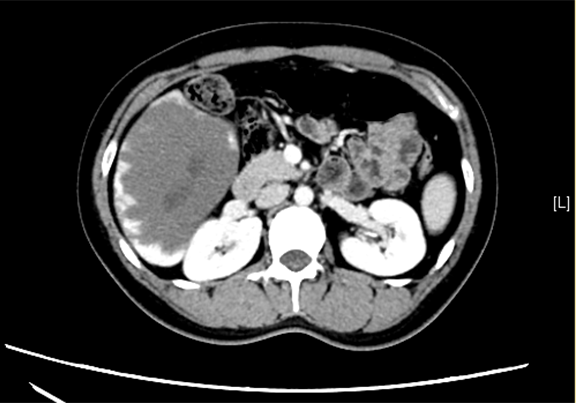

现病史:患者1月前无明显诱因出现右上腹饱胀感,伴右侧肩背不适,伴恶心、嗳气,伴头晕、乏力,无发热,无心悸,无呕吐、呕血,无反酸、烧心,无心慌、胸闷、胸痛,无咳嗽、咳痰,无腹泻、便秘,于当地医院就诊,行“抗炎”治疗(具体不详),疗效不佳。今患者为求进一步治疗,遂来我院,门诊行上腹部增强CT检查示:肝右叶巨大占位,血管瘤可能性大。

辅助检查: 下腹部增强CT示:肝右叶巨大占位。

术前CT检查:动脉期

静脉期

平衡期